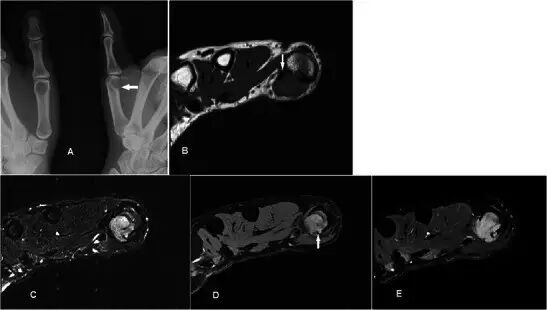

腱鞘巨细胞瘤Giant cell tumour of tendon sheath GCTTS是常见的肿瘤,通常在30-50岁时表现为无痛的肿块,具有轻微的女性偏好。 它们通常存在于与退行性关节相关的手或脚中,并且被认为是对邻近炎症的反应性损伤而不是真正的肿瘤[40]。 GCTTS在组织学上是良性的,但是在10-20%的病例中,在平片上可以看到相邻骨的压力变化[41](图13a)。MR显示与关节和腱紧密相关的损伤,主要是T1w序列上的低信号和T2w序列上的中等至稍高的信号(图13b-e)。 GRE序列上可见典型的异常图像,因为血铁素沉积,这是一个有用的特点[42]。 由于在胶原基质中存在许多增殖性毛细血管,观察到强的增强。 鉴别诊断包括局灶性结节性滑膜炎,其还含有铁氧化物,而更加异质的信号和增强可导致与软组织肉瘤的混淆。

图13.GCTTS在一名23岁的女性,有1年的右拇指肿胀和轻度疼痛的病史。 (a)平片显示在第一掌骨(箭头)的头部的明确的透亮区。 (b)T1w序列显示包围屈肌腱长肌的中间信号的分叶皮下病变(箭头)。 (c)病灶在T2w-FS序列上显示不均匀高信号。 在下面的骨头上有压力侵蚀。 (d)在GRE序列(箭头)上证明了易感性的Foci。 (e)有积极和相当均匀的增强